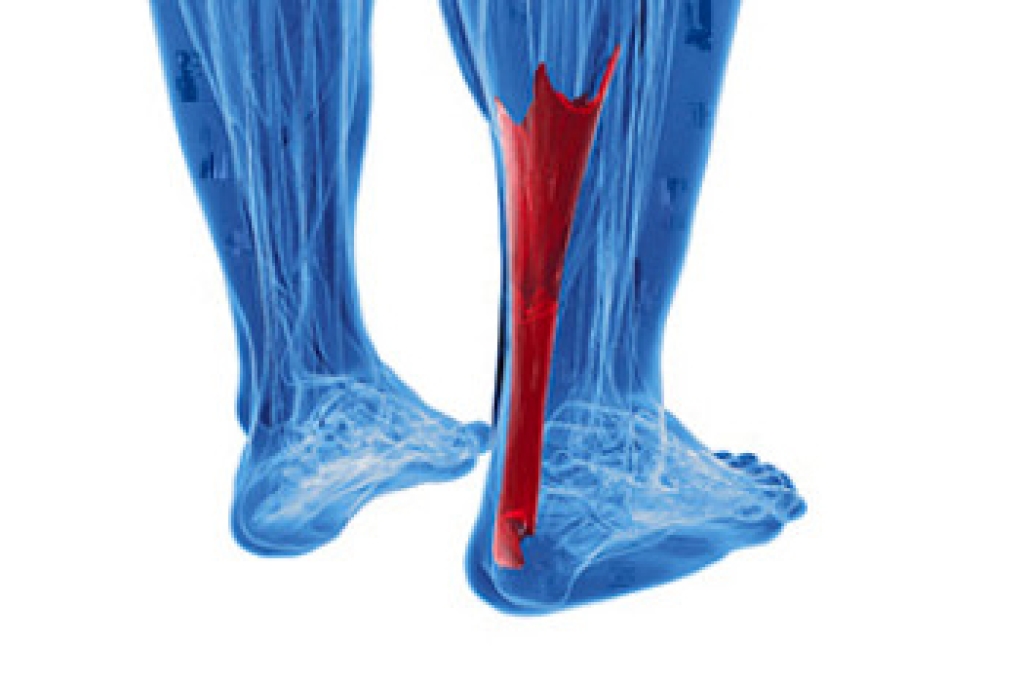

Causes and Symptoms of Achilles Tendonitis

Achilles tendonitis occurs when the thick tendon that connects the calf muscles to the heel bone becomes inflamed from overuse or strain. This tendon plays a key role in walking, running, and pushing off the toes, which makes it vulnerable to injury from repetitive motion or sudden increases in activity. Common causes of Achilles tendonitis include running on hard surfaces, training without proper warm-up, and wearing shoes that lack adequate support. Flat feet, bone spurs on the heel, and certain health conditions can increase the risk of Achilles tendon irritation. Symptoms include pain or stiffness in the back of the ankle, swelling, warmth, and difficulty standing on the toes. Morning stiffness is especially common. If left untreated, inflammation may progress to tendinosis, where the tendon begins to degenerate. In severe cases, a rupture may occur and require surgery. If you are experiencing symptoms of Achilles tendonitis, it is suggested that you make an appointment with a podiatrist for an exam and treatment.

What Is the Achilles Tendon?

The Achilles tendon is a tendon that connects the lower leg muscles and calf to the heel of the foot. It is the strongest tendon in the human body and is essential for making movement possible. Because this tendon is such an integral part of the body, any injuries to it can create immense difficulties and should immediately be presented to a doctor.